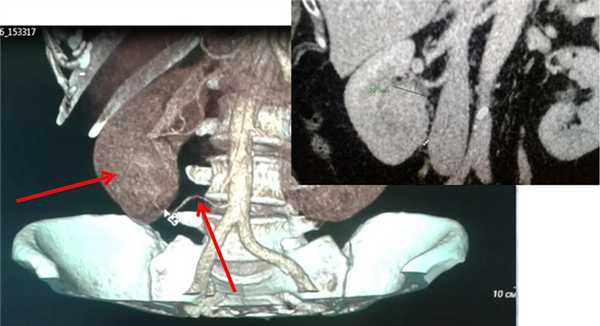

В случае, если опухоль распространяется в просвет почечной вены и/или в нижнюю полую вену, лапароскопический вариант операции возможен, однако он чаще, чем обычно, требует перехода на большой разрез при технических сложностях.

о Прямое инфильтрирование почечной вены (ПВ) (20-35%), нижней полой вены (НПВ) (4-10%), прилежащих мышц и внутренних органов